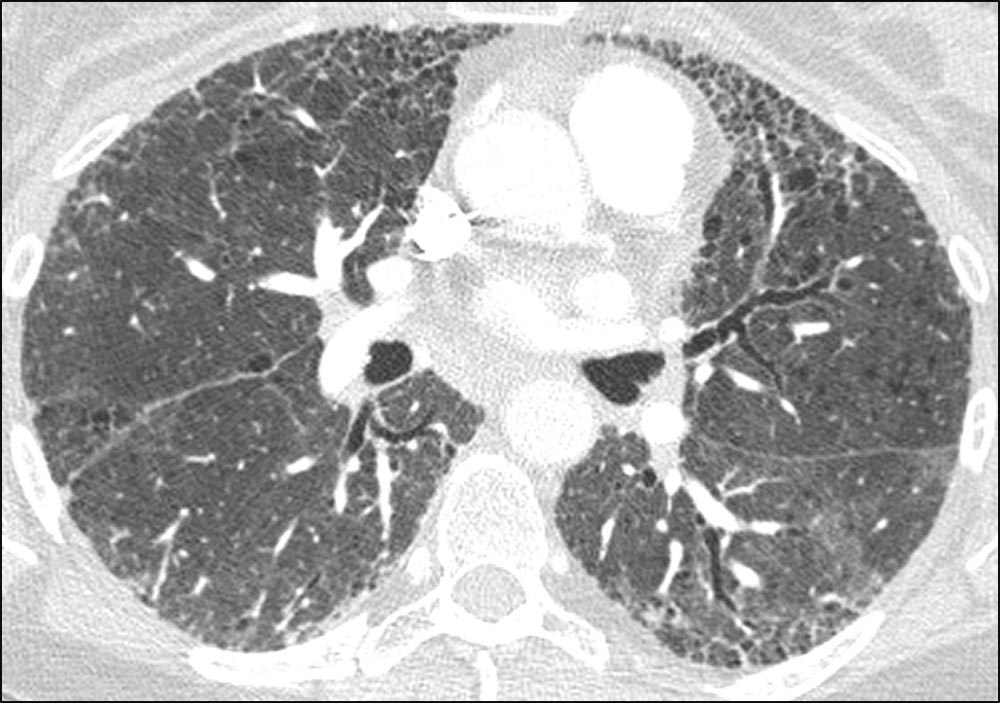

Axial HRCT showing subpleural honeycombing at the bases of the lung in a patient with IPF. On HRCT, honeycomb cysts appear as enlarged airspaces that are often irregular in size, share thick walls, and are stacked upon one another.1 The cysts are typically 3-10 mm in diameter but can be as large as 2.5 cm.1,2 Honeycombing results from the deposition of dense collagen fibers that destroy the characteristic alveolar structure,2 and is typically representative of end-stage lung disease.1 Subpleural, peripheral honeycombing with reticulation in the absence of significant ground glass opacity, consolidation, or non-honeycomb cysts is strongly suggestive of usual interstitial pneumonia (UIP).